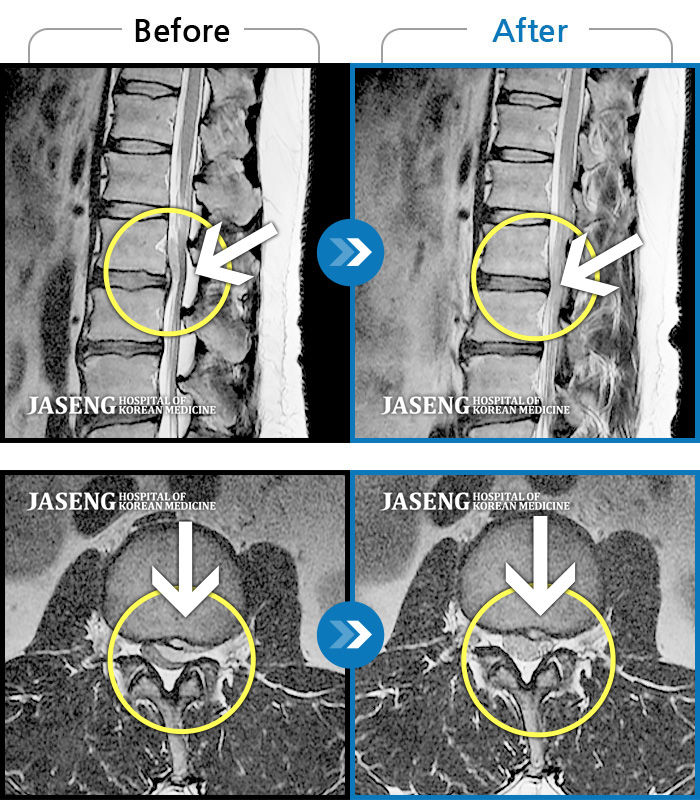

Before

After

환자에게 사전 동의를 받아 동일 조건에서 촬영되었습니다.

개인에 따라 치료 후 부작용이 발생할 수 있으니 의료진과 상담 후 치료를 진행하시기 바랍니다.